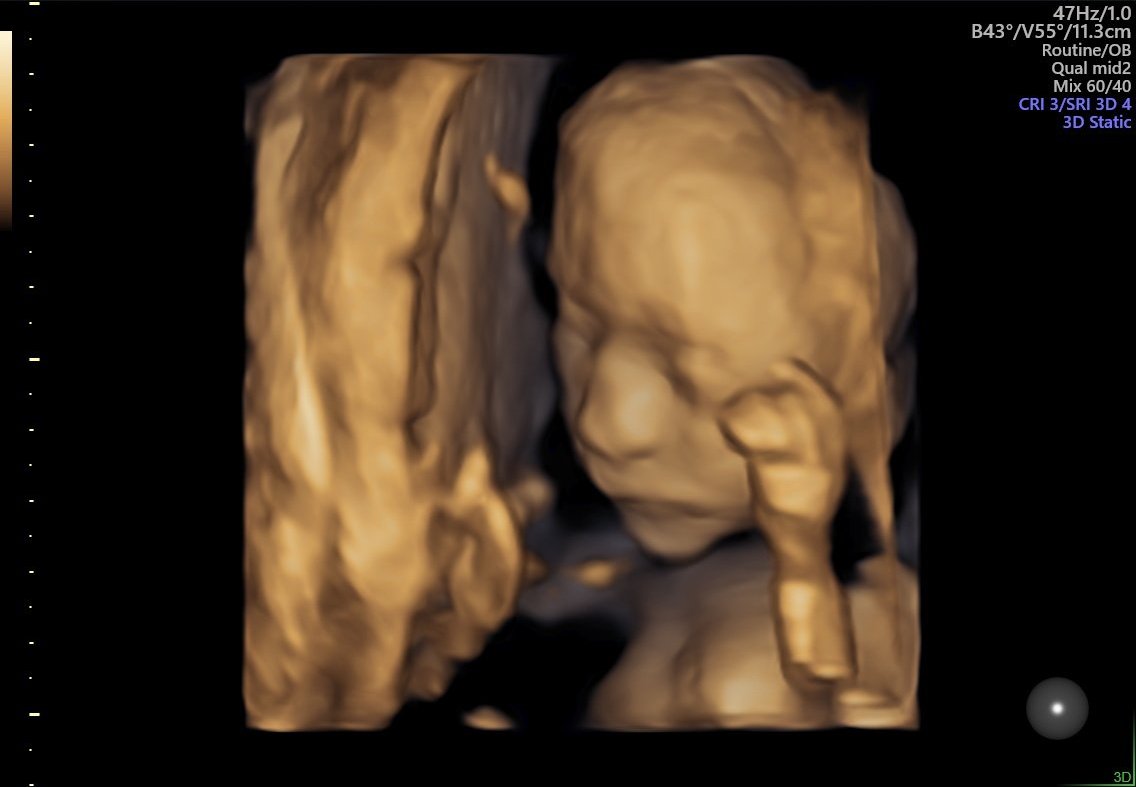

Ето я и моята кукличка от днес Докторката каза, че ще се окаже голяма мислителка 😁 460гр, 21+6 съм